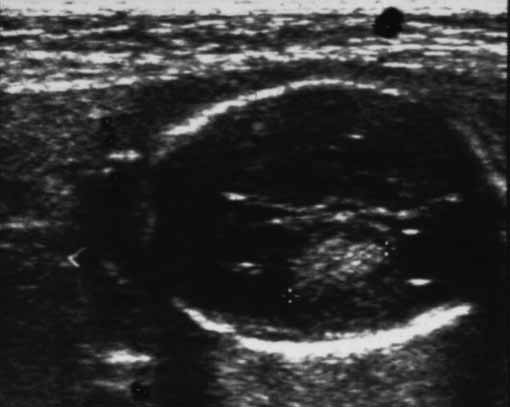

Feto de 34 semanas, de una mujer primigesta de 27 años, que en la semana 25 de gestación , y tras una exploración previa normal, se le detectó por ecografía una masa intracraneal en región témporo – parietal derecha que parecía depender del propio tejido cerebral haciendo impronta en el ventrículo lateral, sin que en ese momento existieran desviaciones de la línea media.

Los ventrículos cerebrales , núcleos de la base y cerebelo presentaban una morfología normal.. La masa intracerebral aumentó de tamaño en las siguientes semanas produciendo una gran desestructuración del cerebro con extensión al otro ventrículo, observándose en su interior una formación hipoecogénica que sugería una malformación o fístula arterio-venosa. Con los diagnósticos clínicos de masa intracerebral; hidrops fetal y feto no viable, se induce el parto con PGE 2 intracervical . Al no producirse el parto espontáneo se realizó una cesárea, extrayéndose un feto varón de 4700 gr con latido cardíaco negativo.